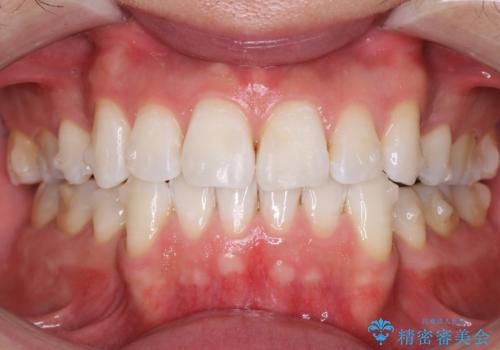

矯正中のオフィスホワイトニング

- 他院にてインビザライン矯正をされており、ホワイトニングのメンテナンスをご希望で来院されました。

インビザラインのアタッチメントと呼ばれる材料が歯の表面に付いていたためホワイトニング後は色むらになる可能性をご説明し、納得していただいた上で施術を行いました。

今回はエクセレントコースを行いました。ホワイトニングの施術経験があったため元々歯の色は明るめでしたが、施術後はより一層トーンがあがり、喜んでいただけました。